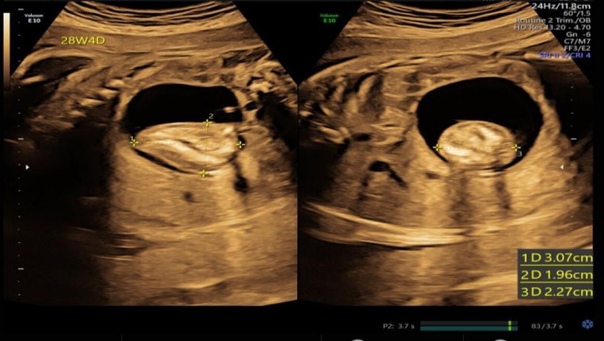

Жалобы на заложенность в ушах. Ранее у пациентки была выявлена ретркация барабанной перепонки, рекомендовано выполнять пользу Вальсальвы, что временно уменьшало ощущение заложенности.

В течение 6 лет пациентка выполняла упражнение 4 раза в день ежедневно.

При осмотре: в толще барабанных перепонок пузырьки воздуха, признаков отека или воспаления нет. Аудиография: умеренная кондуктивная тугоухость справа, нормальный слух слева.

Вероятнее всего изменения барабанных перепонок вызваны за счет частого выполнения пробы Вальсальвы.

Рекомендовано снизить интенсивность и частоту выполнения пробы.

При осмотре спустя 1 месяц отмечено улучшение.